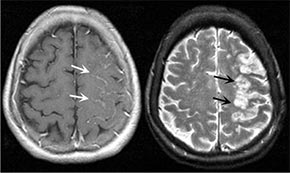

Mrtvice